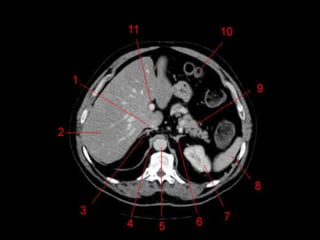

• TC: Tres fases

– Arterial (10 a 20 segundos)

– Fase venosa portal ( 30 segundos )

– Fase venosa hepática (60 segundos)

Técnicas de Imagem •US: Primeiro exame pedido ao: 1) dor no hipocondrio direito; 2) testes de função hepáticas anormais; 3) suspeita de malignidade. • TC: Tres fases – Arterial (10 a 20 segundos) – Fase venosa portal ( 30 segundos ) – Fase venosa hepática (60 segundos) • TC Portografia: Metastases.